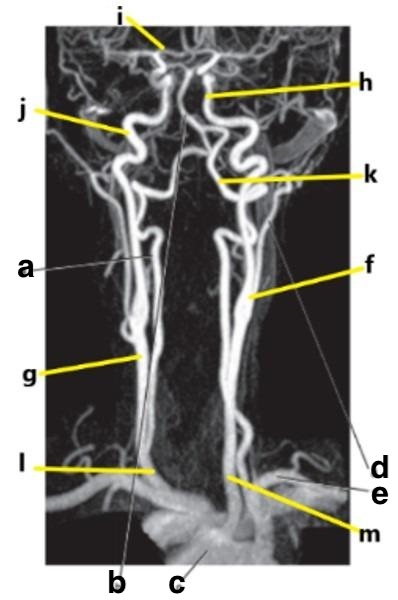

Which letter is the popliteal artery?

A

What is letter k?

Vertebral artery

Which letter is the Right vertebral artery?

f

What is letter m?

Common carotid artery

External carotid artery

left popliteal artery

Basilar artery